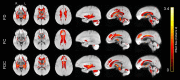

Aging is associated with widespread alterations in cerebral white matter (WM). Most prior studies of age differences in WM have used diffusion tensor imaging (DTI), but typical DTI metrics (e.g., fractional anisotropy; FA) can reflect multiple neurobiological features, making interpretation challenging. Here, we used fixel-based analysis (FBA) to investigate age-related WM differences observed using DTI in a sample of 45 older and 25 younger healthy adults. Age-related FA differences were widespread but were strongly associated with differences in multi-fiber complexity (CX), suggesting that they reflected differences in crossing fibers in addition to structural differences in individual fiber segments. FBA also revealed a frontolimbic locus of age-related effects and provided insights into distinct microstructural changes underlying them. Specifically, age differences in fiber density were prominent in fornix, bilateral anterior internal capsule, forceps minor, body of the corpus callosum, and corticospinal tract, while age differences in fiber cross section were largest in cingulum bundle and forceps minor. These results provide novel insights into specific structural differences underlying major WM differences associated with aging.